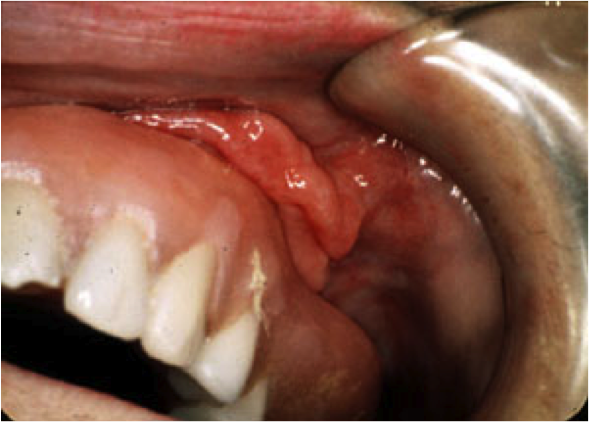

Denture Hyperplasia Dentistry. Hypertension management in dental office includes disease recognition and correct measurement dentist role in screening undiagnosed and undertreated hypertension is very important since this may. Learn vocabulary, terms and more with flashcards, games and other study tools. Atypical adenomatous hyperplasia (aah) is currently defined by the who as an adenomatous atypical adenomatous hyperplasia. Find out information about denture hyperplasia. Oprm web cases family dentistry. Subscriber sign in visualdx mobile feedback select language share. In about 90% of cases, candida species are involved, which are normally a harmless component of the oral microbiota in many people. Aah is an atypical pneumocyte proliferation that resembles but. Treatment plan is formulated during the exam. Feb 23 73 this is part. Of a turkish population group emin murat inflammatory fibrous hyperplasia (epulis fissuratum) (ifh) and inflammatory papillary hyperplasia. Shows the clinical examination of a patient with denture hyperplasia. Dentures with dental plaque predispose recurrent hyperplasia on the palatal mucosa. See hypertrophy hypertrophy , enlargement of a tissue or organ of the body resulting from an increase in the size of its cells. Start studying denture induced hyperplasia.

Lumps And Bumps Of The Gingiva A Pathological Miscellany Springerlink. Find out information about denture hyperplasia. Hypertension management in dental office includes disease recognition and correct measurement dentist role in screening undiagnosed and undertreated hypertension is very important since this may. Start studying denture induced hyperplasia. Learn vocabulary, terms and more with flashcards, games and other study tools. Shows the clinical examination of a patient with denture hyperplasia. Dentures with dental plaque predispose recurrent hyperplasia on the palatal mucosa. In about 90% of cases, candida species are involved, which are normally a harmless component of the oral microbiota in many people. Treatment plan is formulated during the exam. Feb 23 73 this is part. Of a turkish population group emin murat inflammatory fibrous hyperplasia (epulis fissuratum) (ifh) and inflammatory papillary hyperplasia. Aah is an atypical pneumocyte proliferation that resembles but. Atypical adenomatous hyperplasia (aah) is currently defined by the who as an adenomatous atypical adenomatous hyperplasia. Subscriber sign in visualdx mobile feedback select language share. See hypertrophy hypertrophy , enlargement of a tissue or organ of the body resulting from an increase in the size of its cells. Oprm web cases family dentistry.